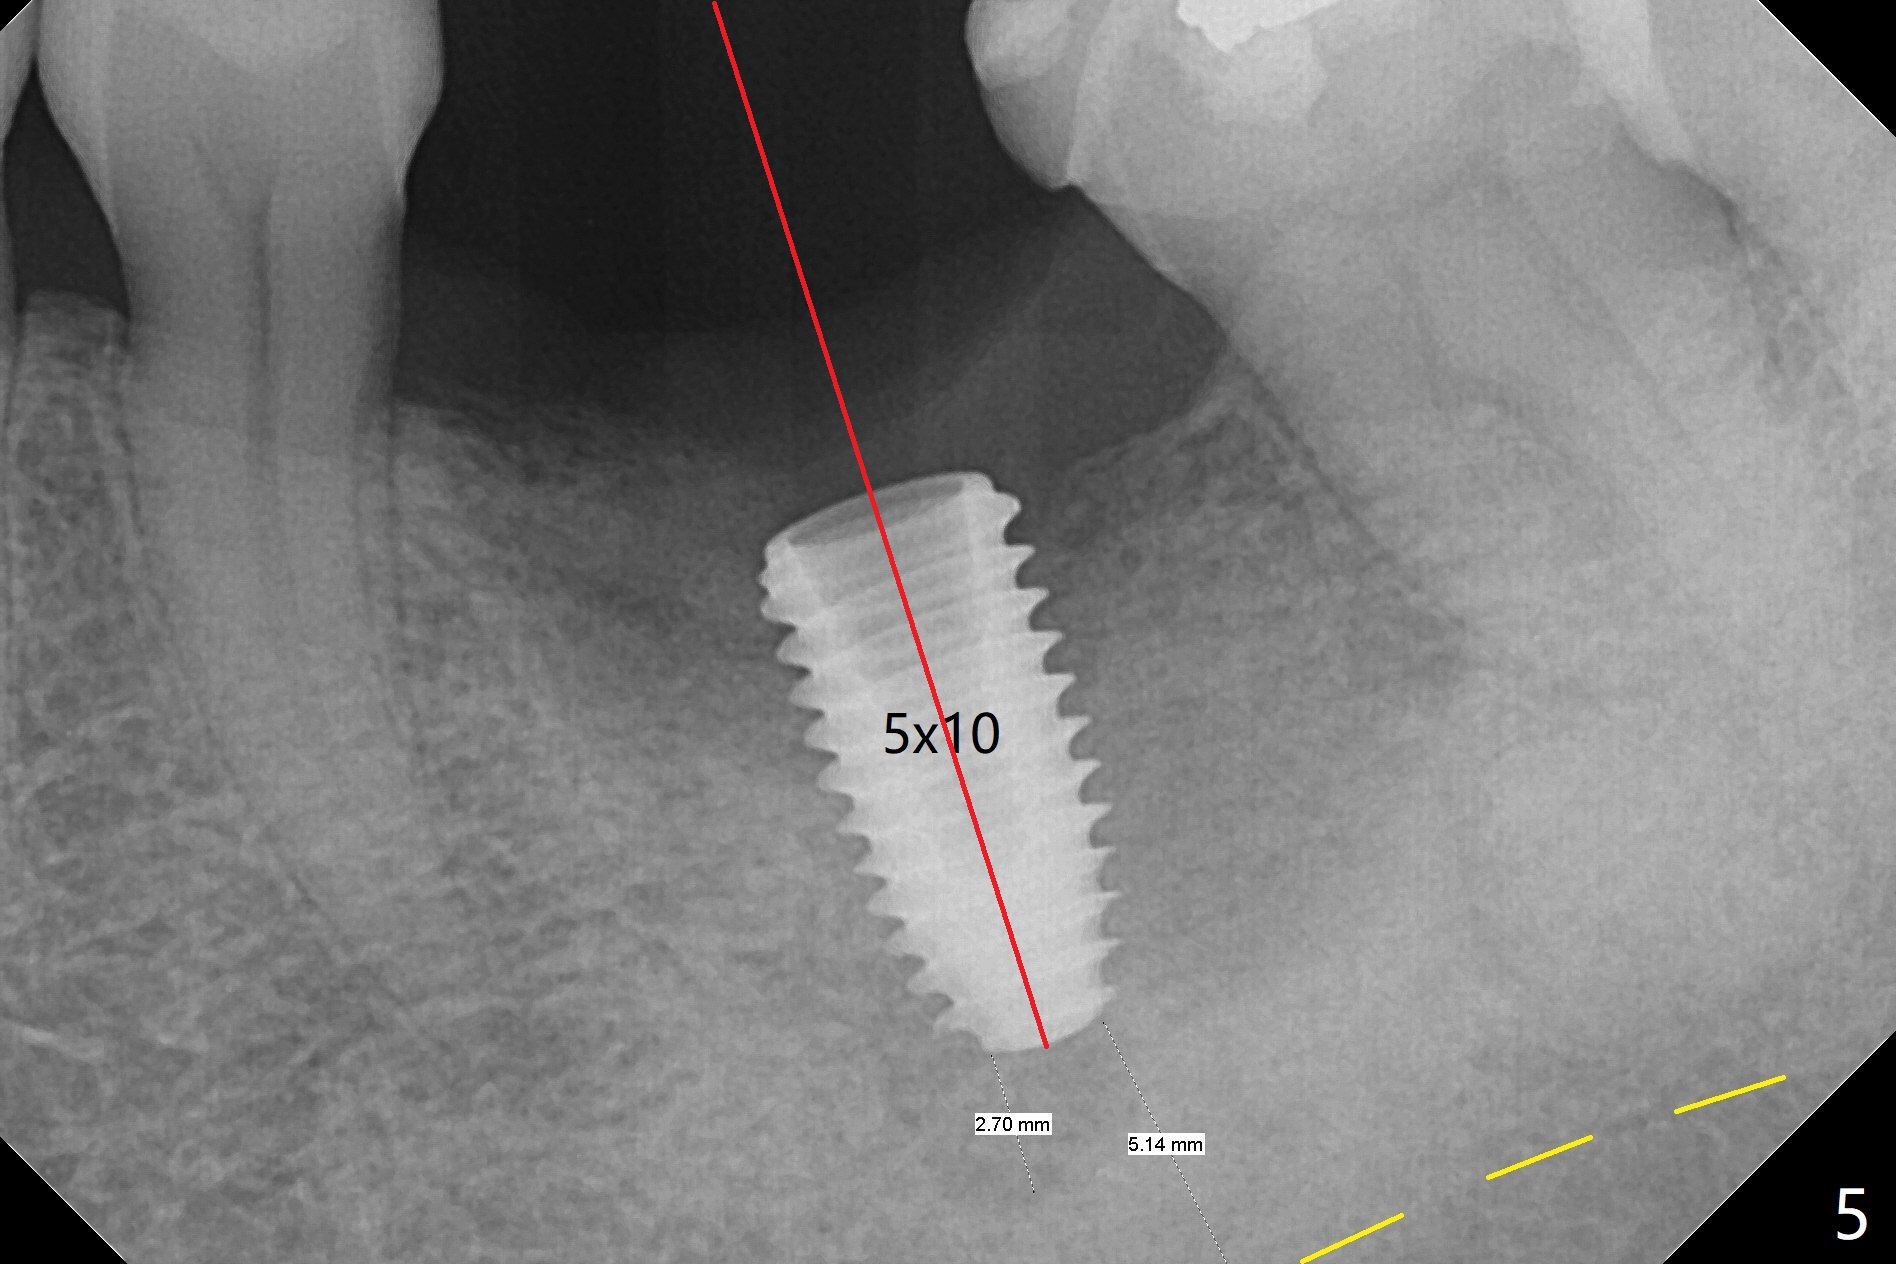

CT taken 4-5 months post extraction shows the outline of the socket at #19 (Fig.1 pink and red dashed line). By the time of surgery (6-7 months post extraction), the ridge looks narrow (Fig.2). In fact the socket does not heal (Fig.3). Osteotomy starts at the mesial border of the socket (Fig.4). When a 5x10 mm dummy implant is placed, the axis begins to be tilted distally (Fig.5 red line), which is more obvious when a definitive longer implant (5x11.5 mm) is placed (Fig.6,7). Osteotomy (Fig.1 arrow) at the mesial slope of the socket (red dashed line) should be initiated more mesial to compensate for the distal drifting while osteotomy is being increased and the implant is being placed. The distal defect is filled with Vanilla graft. Probably due to the mesial slope and the distal defect, the primary stability is <10 Ncm. A healing screw is placed with Vanilla allograft/autogenous bone. The bone forms coronal to the implant 4 months postop (Fig.8 *), which is removed for uncover. The mesial gingival embrasure of the permanent crown is large (Fig.9 *), as related to the mesial undercut associated with a 5.7x4 mm A 15 degree angled abutment (Fig.10). Reduction in the undercut should be able to help lab decrease the gingival embrasure (Fig.11 red line). The bone density around the implant increases with distinct trabecular pattern consistent with stress 5 months post cementation (1 year postop, Fig.12).